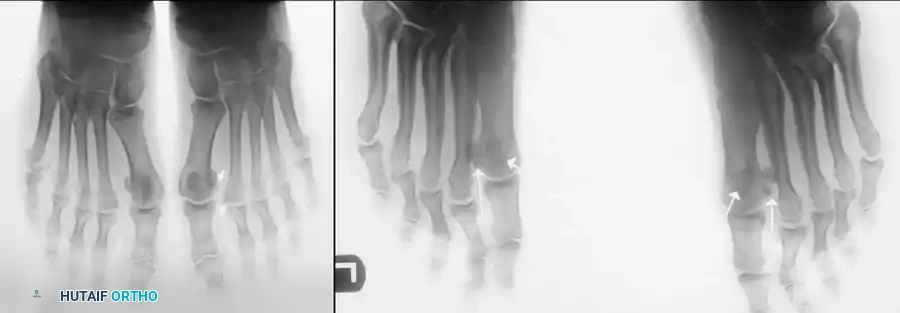

Fig. 78-95 A, Standing anteroposterior view of both feet on the same cassette allows comparison of the sesamoids. This is especially helpful if a fracture is suspected but a bipartite sesamoid is present. Accessory sesamoids (arrows) are a normal, although uncommon, finding. B, Oblique view profiles the fibular sesamoid. Note the cystic fibular sesamoid on the right foot. This probably represents an old fracture through the syndesmotic union of a bipartite sesamoid.